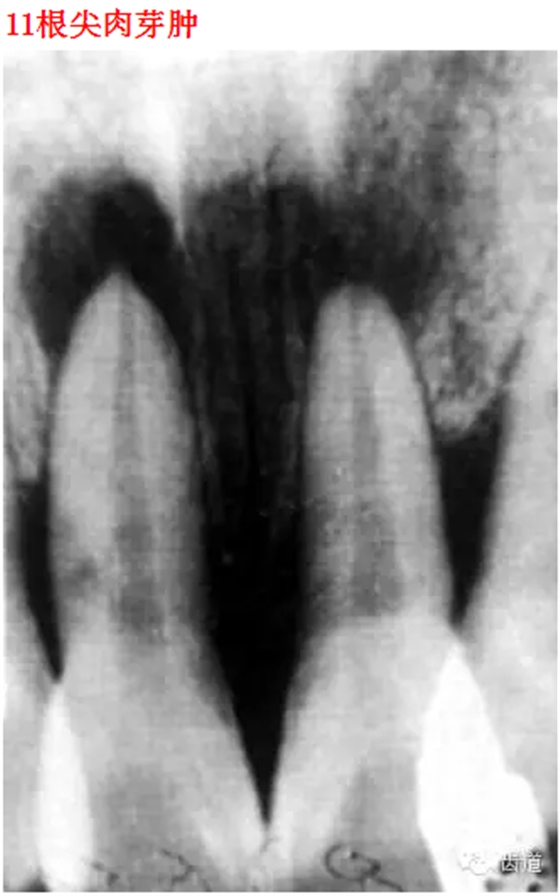

首頁(yè)口腔影像 26種口腔病變X光片

26種口腔病變X光片